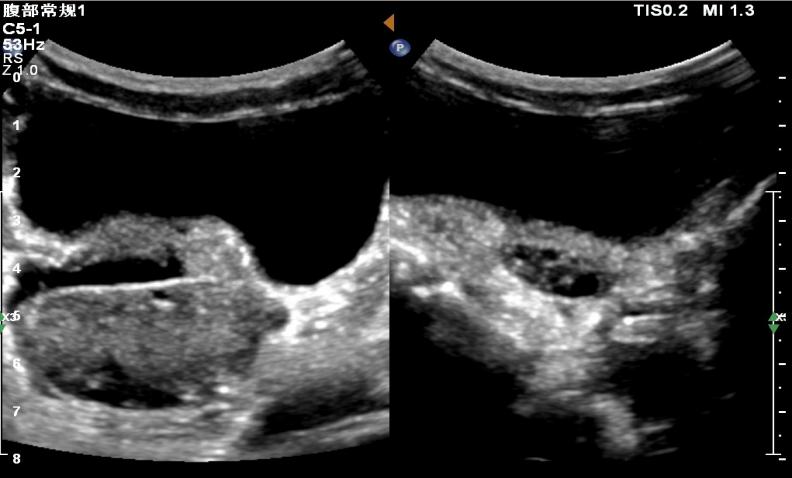

据西安市儿童医院公众号26日消息:5岁的彤彤(化名)因跳绳后下腹部疼痛难耐,当地医院初步诊断为急性阑尾炎。急诊来该院进一步复查B超,超声科医生却发现了更为严重的问题——卵巢扭转。

医院随即安排进行急诊手术,术中发现右侧卵巢发紫,顺时针扭转720°,即对右侧卵巢进行了切除。